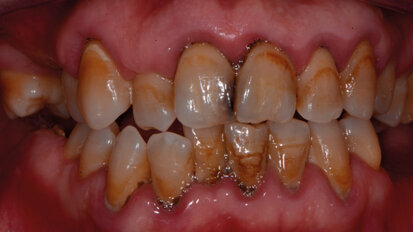

Carie e brown spot: il recupero dell’estetica del sorriso tra debridment, sbiancamento, infiltrazioni, ricostruzioni. Case report

Le tecnologie avanzate permettono la scelta di percorsi terapeutici personalizzati per ogni esigenza clinica ed emotiva. Progettare protocolli operativi ...